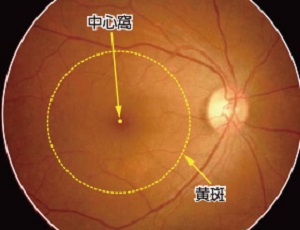

黄斑・中心窩について

黄斑とは、網膜の中心部にあり、視力ともっとも深いかかわりを持っています。物を見たときのその物の大きさや形、奥行きなど、視覚情報の大半が、黄斑で認識されています。ここで障害が起こると、当然ながら視力の低下が引き起こされます。 黄斑のさらに中心には、「中心窩」があります。こちらはさらに重要な部分であり、障害されたときにはより大幅な視力低下を招きます。

黄斑とは、網膜の中心部にあり、視力ともっとも深いかかわりを持っています。物を見たときのその物の大きさや形、奥行きなど、視覚情報の大半が、黄斑で認識されています。ここで障害が起こると、当然ながら視力の低下が引き起こされます。 黄斑のさらに中心には、「中心窩」があります。こちらはさらに重要な部分であり、障害されたときにはより大幅な視力低下を招きます。

眼底の正面図(正常な眼)

黄斑の範囲については、厚生労働省の網膜脈絡膜・視神経萎縮症研究班による『加齢黄斑変性の分類と診断基準』に準拠しています。

黄斑の範囲については、厚生労働省の網膜脈絡膜・視神経萎縮症研究班による『加齢黄斑変性の分類と診断基準』に準拠しています。

写真提供:日本大学 湯澤 美都子先生